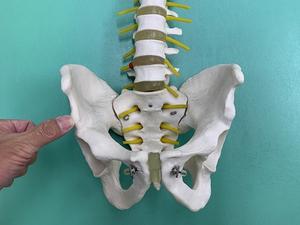

「下前腸骨棘剥離骨折」とは、骨盤前面の腸骨という骨の出っ張りには、

上前腸骨棘と下前腸骨棘と呼ばれる突起があります。

下前腸骨棘.jpg

上前腸骨棘には大腿筋膜張筋・縫工筋、下前腸骨棘には大腿直筋という、

ジャンプ動作、ボールを蹴る動作時に作用する筋肉が付着しており、

急な動作の繰返し、急激な収縮作用による牽引力によって、筋肉の付着部が炎症を起したり、

上前腸骨棘、下前腸骨棘部が剥離骨折を起こすスポーツ障害です。